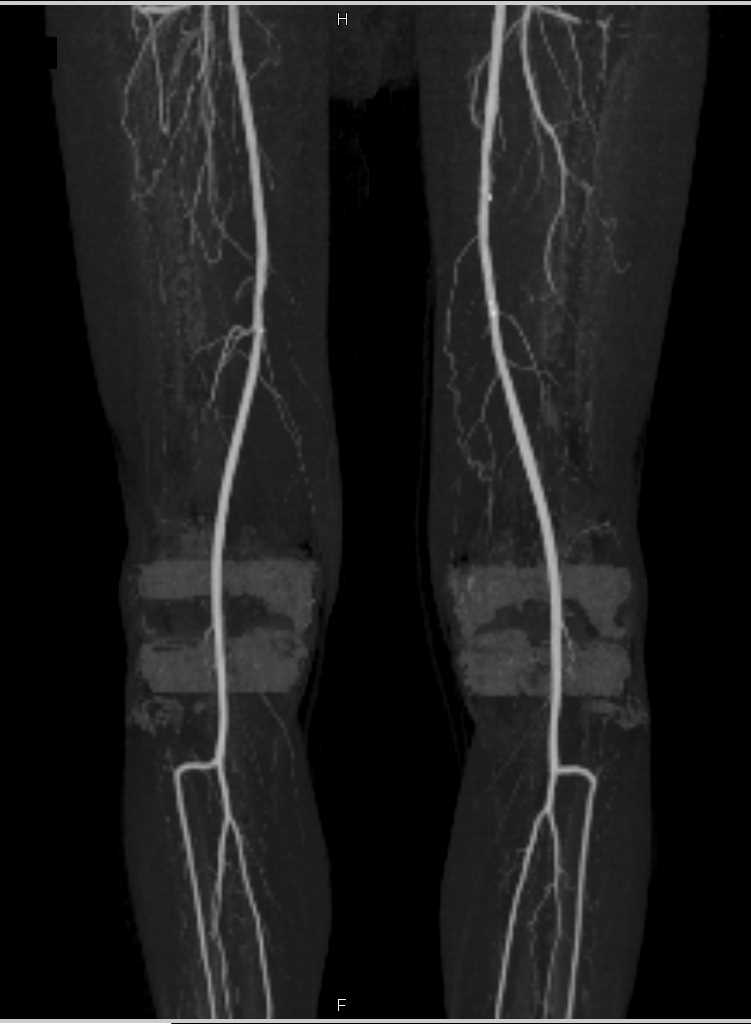

Occlusion of the Right Common Iliac Artery